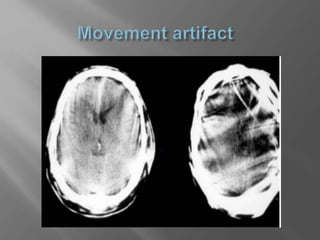

 Look atold images and reports  Check for movement artifacts and medical artifacts  Do not view only a single slice in isolation  If you suspect brain stem pathology ,consider MRI

 Check for movement artifacts and medical

artifacts